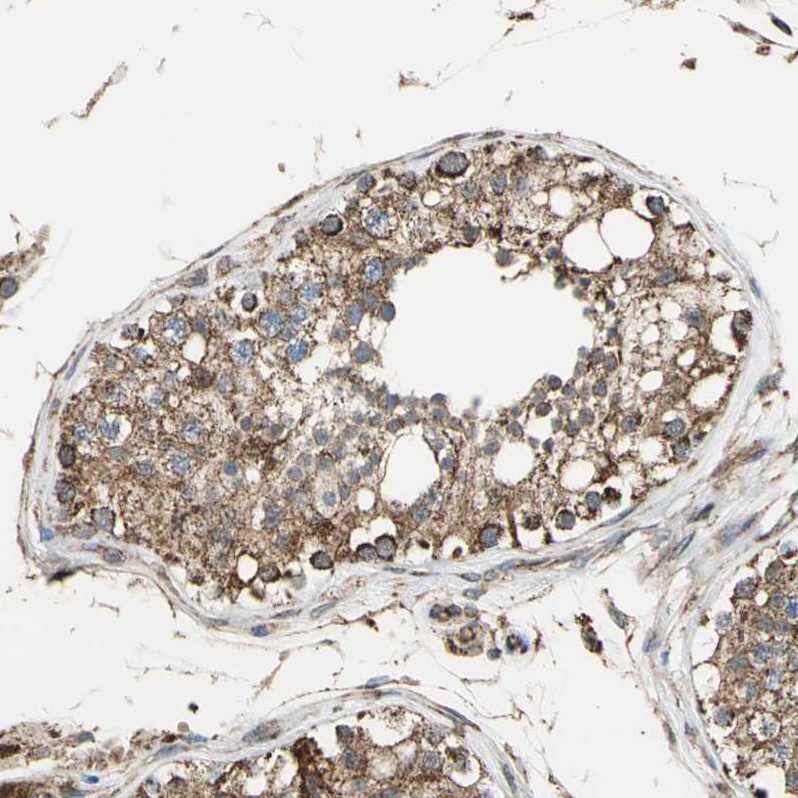

Immunohistochemical staining of human cerebral cortex, gastrointestinal, kidney and testis using Anti-MRPS22 antibody HPA006083 (A) shows similar protein distribution across tissues to independent antibody HPA007830 (B).